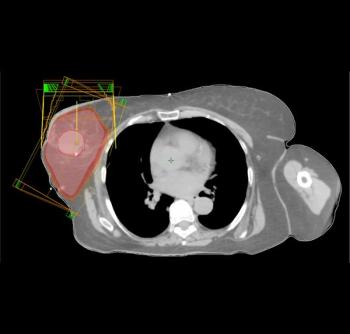

Researchers have developed a nomogram to help calculate which breast cancer patients may be appropriate candidates for accelerated partial breast irradiation.